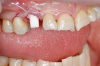

Fig 19. Atraumatic extraction.

Figure 19

Occasionally dentists are presented with extreme challenges with long-term restorations and replacing missing teeth. Dentists must evaluate the patient's condition, develop optimum long-term oral health, and attempt to meet the patient's expectations. Figure 18 showed a class III malocclusion with deep bite, multiple abfractions, and less-than-ideal occlusal plane, but the patient wanted to replace his maxillary right canine only. A discussion with the patient regarding occlusal disharmonies and comprehensive recommendations for full-mouth rehabilitation revealed that the patient had a limited budget for dental care. The patient understood the ramifications of his comprehensive dental needs not being affordable. Decisions were made to atraumatically remove the maxillary right canine (Figure 19) and immediately place a ceramic dental implant (Figure 20). Polytetrafluoroethylene (PTFE) 4-0 sutures were placed to help support soft tissues, and then a full-arch Essix-style retainer with a flowable composite facial veneer was used to provide some esthetics during the patient's healing phase (Figure 21). The implant and the retainer were not to be in contactthe retainer may occlude with the opposing dentition and also be passive in relation to the ceramic implant.